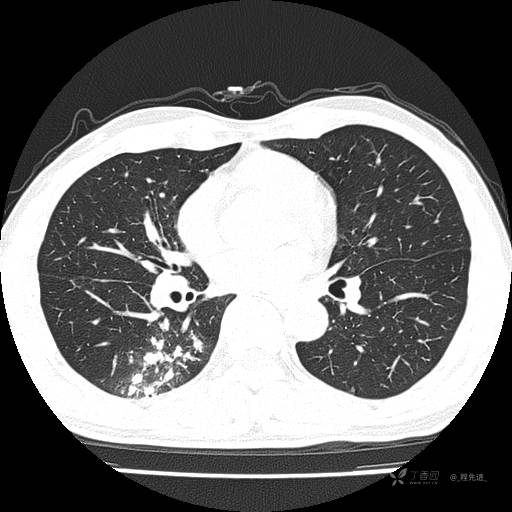

2月特别精彩病例|咳嗽、咳痰20余天,典型病例分享【结果已公布】

患者年龄:51岁

主诉:咳嗽、咳痰20余天

简要病史:20余天前开始出现咳嗽、咳痰症状,阵发性刺激性咳,白色粘痰,不易咳出,无发热,无咯血,无恶心、呕吐等不适,未诊治,咳嗽、咳痰症状持续存在。

体格检查:T:36.3 ℃ P:79 次/分 R:20 次/分 BP:128/64 mmHg,神志清楚,呼吸平稳,双肺呼吸音粗,右下肺闻及细湿性啰音。心率79次/分,节律整齐,各瓣膜听诊区未闻及病理性杂音。腹部未见异常,双下肢无水肿。

辅助检查:我院门诊胸部CT示:如下。心电图:窦性心律;正常心电图。